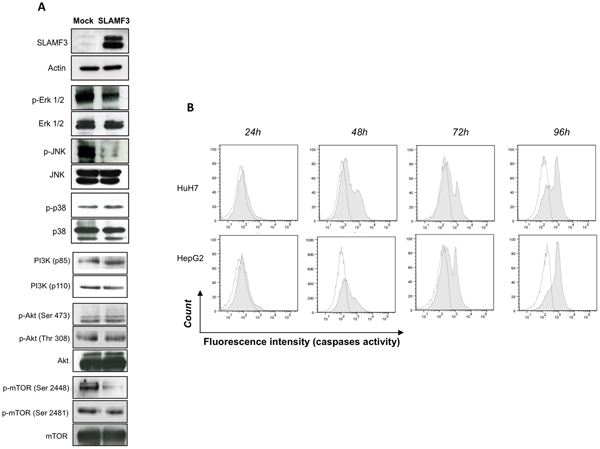

FAM-FLICA Caspase 1, Assay Kit (Cat# AAA12391)

Caspase-8, Monoclonal Antibody (Cat# AAA30210)

Caspase-8, Polyclonal Antibody (Cat# AAA10948)